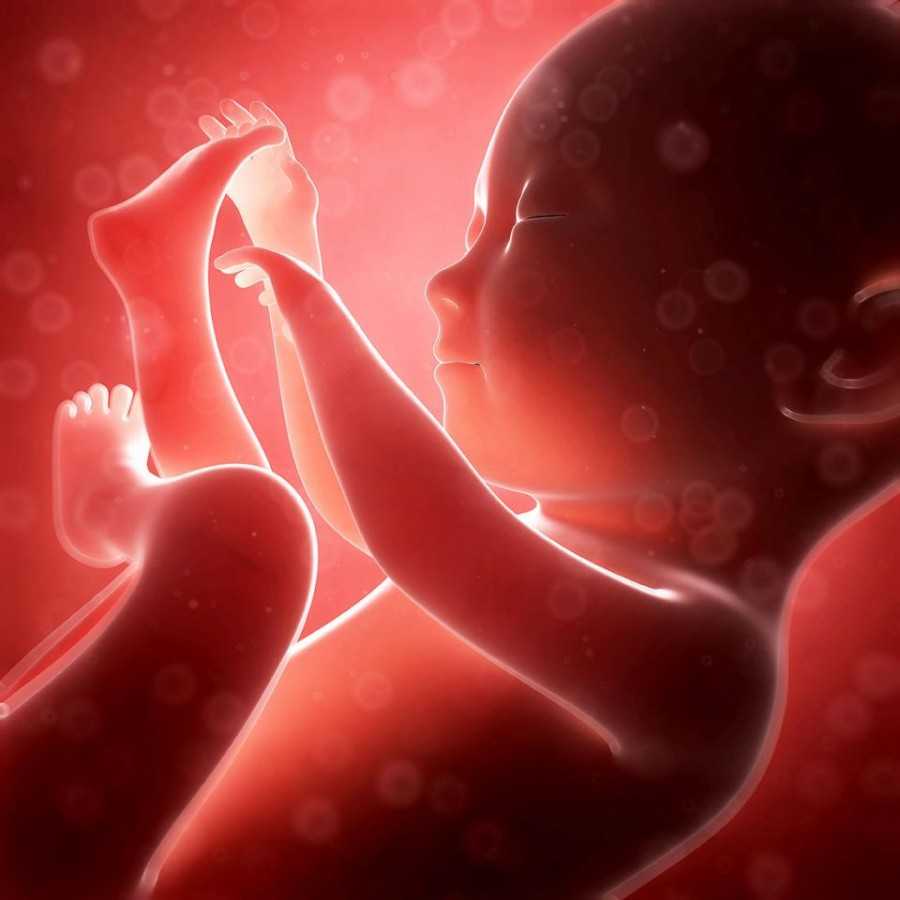

Малыш к 29 неделе беременности от зачатия, по сути, уже сформирован. Если ему вздумается родиться на этом сроке, он уже сможет дышать сам, хотя все равно будет считаться недоношенным.

Основная «работа» малыша в этот период — накапливать подкожный жир. С его помощью он будет защищен от перепадов температуры, ведь в животе у мамы намного теплее, чем вне его.

Голова ребенка по отношению к телу уже не кажется большой, пропорции приблизились к привычным нам. У крохи есть ресницы, брови, волосы на макушке.

С каждой неделей малыш становится все сильнее, он может весьма болезненно толкаться ручками и ножками, но это не беда – главное, чтобы он почаще шевелился. Иногда мама может ощутить подобие спазмов в животе – это малыш икает. Такое случается, когда околоплодная жидкость попадает ребенку не в то горло.

На 29 неделе беременности от зачатия печень малыша продолжает развитие. Она «учится» продуцировать желчь, которая понадобится крохе для переваривания пищи, а именно – жиров. Формируется и поджелудочная железа, в будущем она будет производить ферменты для расщепления углеводов, белков и жиров, а также станет вырабатывать инсулин.

Постепенно на этом сроке вырабатывается предпочтительная поза малыша – предлежание. Он может разместиться головой вниз – чаще всего так и происходит. Реже кроха лежит тазом или ножками вниз, это называют тазовым предлежанием. В ряде случаев он занимает позицию поперек матки — поперечное предлежание. В зависимости от позы ребенка врачи рекомендуют маме естественные роды или кесарево. Однако пока думать об этом женщине рано, ведь ребенок может еще перевернуться.

На 29 неделе от зачатия малыш весит примерно 1400-1600 граммов, а его рост — 39-40 см. Иногда врачи сравнивают его параметры с экзотическим фруктом помело (также называют помпельмусом). Это такой грейпфрут–переросток.

- Тельце плода выглядит почти так же, как у новорожденного, т. е. является достаточно пропорциональным.

- Содержание жировой ткани достигает 4% от общей массы тела малыша.

- Начинает формироваться зубная эмаль, но зубки пока еще расположены в глубине десен, а процесс их прорезывания активизируется через несколько месяцев после появления на свет ребенка.

- Из носовых ходов плода удаляются слизистые пробки, таким способом организм готовится к самостоятельному дыханию. Сейчас носовая полость омывается амниотической жидкостью, что способствует развитию обоняния у будущего малыша.

- Расположение плода на данном сроке, как правило, головное. При ягодичном предлежании еще есть шанс, что малыш правильно разместится в животике.

- Шевеления малыша хорошо ощущаются женщиной, ведь плод часто совершает движения ручками и ножками, периодически икает, поворачивает голову.